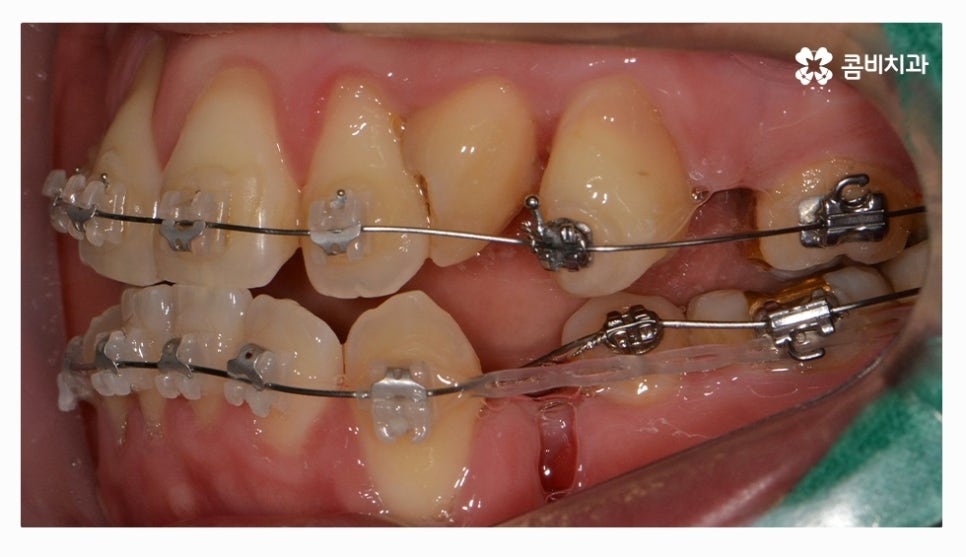

오늘 소개드릴 환자분은 윗니와 아랫니가 제대로 맞물리지 않는

부정교합 사례이며 클리피씨교정을 통해서 치료가 진행된 사례라고 할 수 있어요.

부정교합 환자분들의 경우 발치나 수술이 필요한 경우가 있는데

치아교정을 진행할 때 치아의 이동 공간을 고려해야 하므로

치간 삭제나 어금니 후방 이동으로도 치아 이동 공간이 부족하다면

발치를 필수적으로 해야 하는 경우가 있어요.

전체교정을 하시는 분들의 경우 보편적으로 많이 선택하시는

교정 장치는 클리피씨교정이라고 할 수 있을 정도로 선호도가 높으며

클리피씨교정은 자가 결찰 장치로 통증 감소 및 교정 기간을

단축시킬 수 있으며 관리가 편리하다는 장점도 갖고 있어요

클리피씨교정은 세라믹 재질이기 때문에 심미적으로도 우수한 편이며

브라켓과 와이어 고정을 위한 철사를 사용하지 않기 때문에 철사로 인해 찔리거나

입안이 뜯겨 피가 나는 경우를 예방할 수 있는데요.

클리피씨교정은 철사를 쓰지 않고 특수 클립이 내장되어

클립을 이용하여 와이어를 고정하고 열고 닫을 수 있기 때문에

교정 장치로 인한 불편함이 줄어들 수 있으며 철사를 사용하지

않는 것만으로도 보다 편안함을 느낄 수 있지만 치아를 적은 힘으로

지속적으로 이동시켜서 상대적으로 통증이 적고 치과 내원 횟수도 줄일 수 있어요.

위 환자는 총 치료기간 약 30개월이 소요되었으며

개인에 따라 치료 기간 및 결과가 차이가 있을 수 있고,

개인에 따라 출혈 및 부작용이 발생할 수 있습니다.